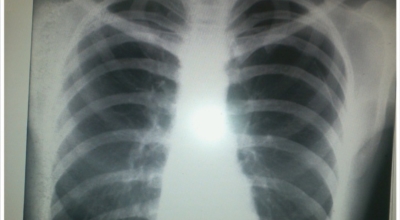

8. 갈비뼈 금간 증상 - 근육통과 금이 간 경우 차이는 거의 없습니다.

일반인이 근육통과 금이 간 경우의 차이는 거의 판별하기 힘들어요. 갈비뼈라고 하는 부분이 눈에 보이도록 붓는 것도 아니고, 멍이 들어서 아픈것도 아니기 때문이지요. 가장 정확하게 판별하는 방법은 엑스레이를 찍는 방법이지요.